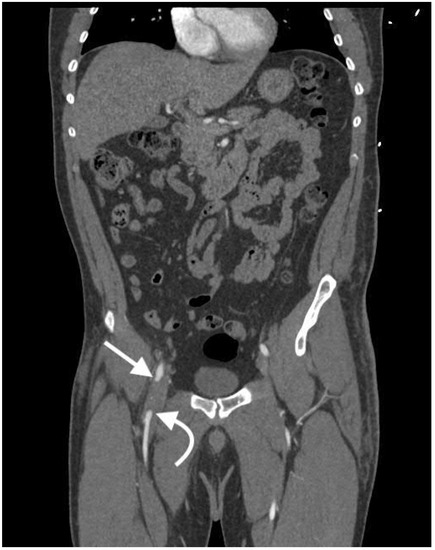

2.4.1. Active Arterial Extravasation